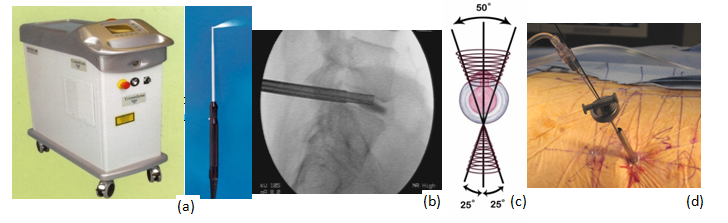

Figure 13a, b, c, d Holmium YAG laser generator, probe, on fluoroscopic view, inverted cone shape maneuver, laser thermodiskoplasty procedure.